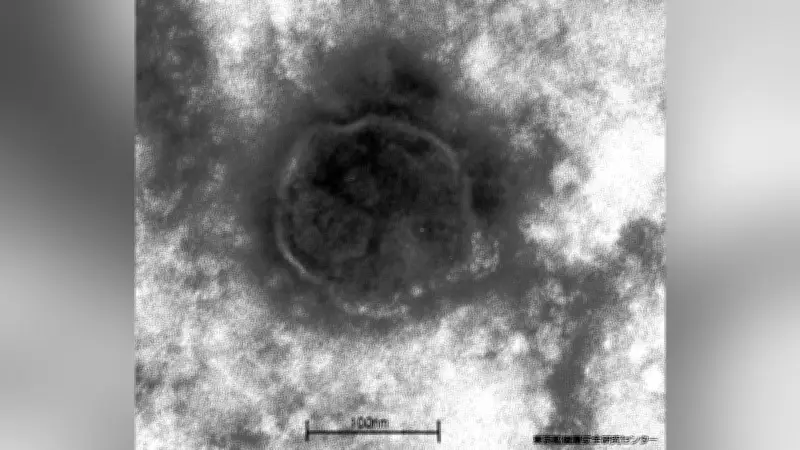

感染力が強い麻疹(はしか)の患者数が、今年に入って3月29日までで197人(速報値)になったことが、国立健康危機管理研究機構(JIHS)の7日発表で明らかになりました。この数字は、コロナ禍後で最多となった前年同時期の60人と比べて3倍以上に達しており、感染拡大が深刻化している状況を示しています。